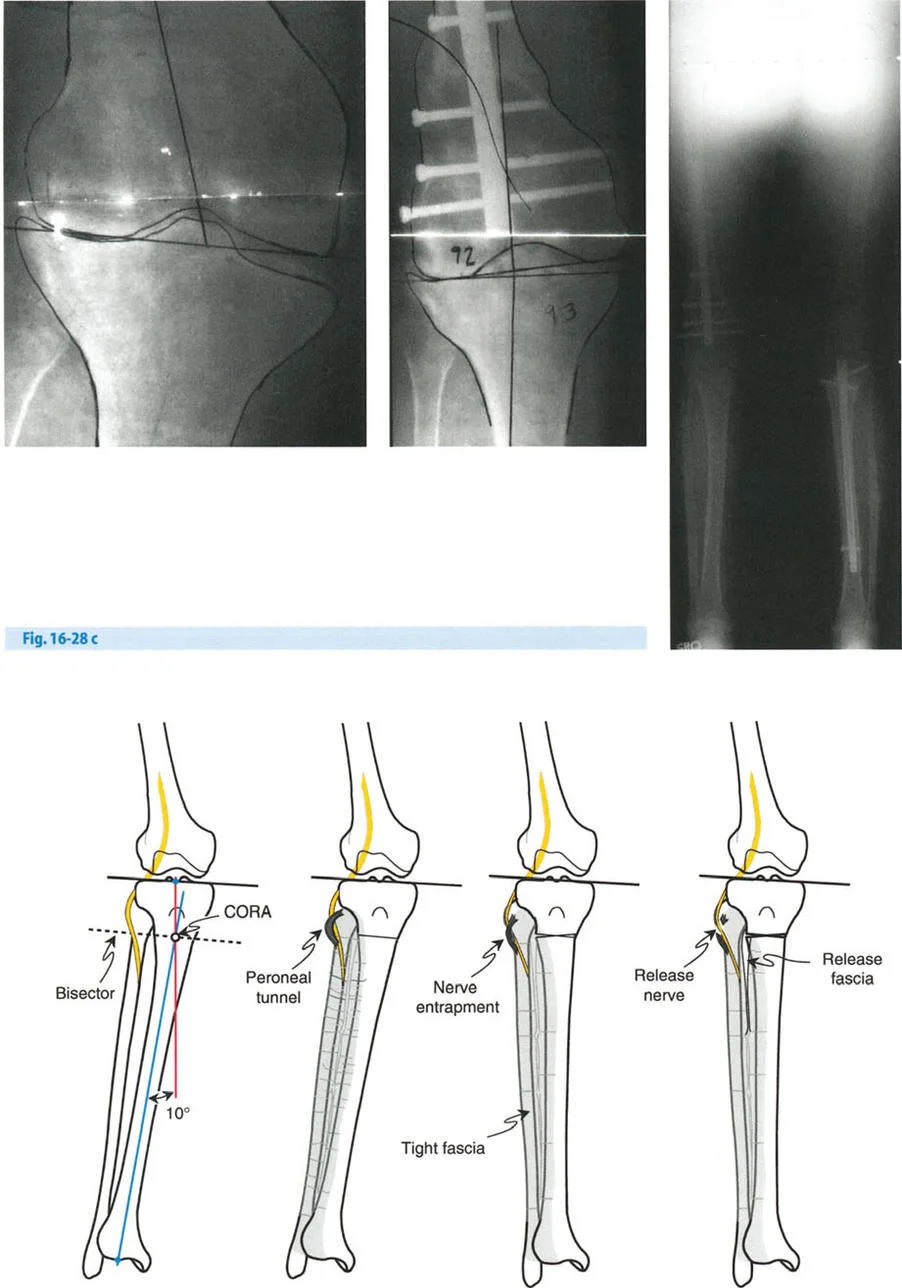

- مخاطر العصب الشظوي: التصحيح الحاد للانحراف الأروح في الساق قد يؤدي إلى شد العصب الشظوي، مما قد يسبب إصابة العصب أو متلازمة الحيز. قد يُنصح بإجراء تحرير وقائي للعصب الشظوي وقطع اللفافة (Fasciotomy) في التصحيحات الكبيرة، أو استخدام التصحيح التدريجي بالتثبيت الخارجي.

- العصب الشظوي (Peroneal Nerve): في تصحيحات الانحراف الأروح الشديد في الساق، قد يكون تحرير العصب الشظوي ضروريًا لتجنب إصابته.